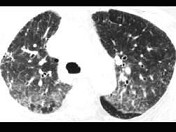

- 单项选择题男,76岁, 咳嗽,呼吸困难半年, CT检查如图,最可能的诊断为 ( )

A、肺结核并肺气肿

B、间质性肺炎

C、矽肺

D、肺部感染

E、农民肺